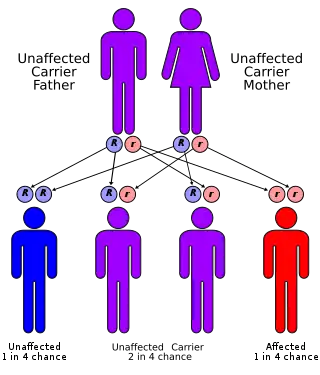

| Alpha-mannosidosis has an autosomal recessive pattern of inheritance Figure 1 | |

Alpha-mannosidosis is a lysosomal storage disorder,[1] first described by Swedish physician Okerman in 1967.[2] In humans it is known to be caused by an autosomal recessive genetic mutation in the gene MAN2B1, located on chromosome 19, affecting the production of the enzyme alpha-D-mannosidase, resulting in its deficiency.[2][3][4] Consequently, if both parents are carriers, there will be a 25% chance with each pregnancy that the defective gene from both parents will be inherited, and the child will suffer from the disease. There is a two in three chance that unaffected siblings will be carriers (Figure 1).[4] In livestock alpha-mannosidosis is caused by chronic poisoning with swainsonine from locoweed.